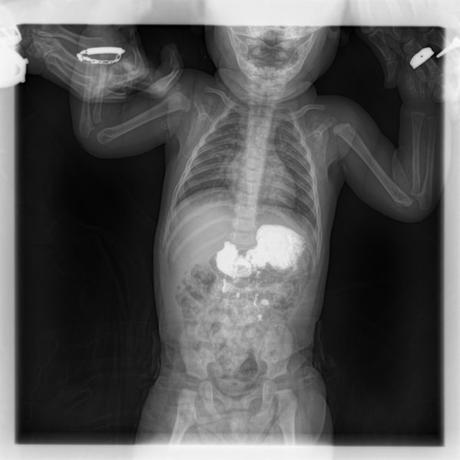

ESTUDIO SOLICITADO: SERIE ESOFAGOGASTRODUODENAL.

Se realiza Esofagograma con material de contraste baritado, por vía oral y por medio de control fluoroscópico se toman distintas proyecciones observando lo siguiente.

Se observa mecánica de la deglución con adecuado paso de medio de contraste de faringe a esófago sin presencia de defectos de llenado depósitos anómalos o fuga del mismo.

ESÓFAGO se observa de situación, calibre y trayecto normal. Contornos regulares y bien definidos. No se observan depósitos anómalos, defectos de llenado o fuga del medio de contraste.

UNION ESOFAGOGASTRICA se observa con calibre y situación normal. Sin observar reflujo a las maniobras de valsalva

ESTOMAGO se observa en su situación habitual, distendido, sin defectos de llenado.

- Actualmente no se demuestra Reflujo gastro-esofágico.

- Estudio de apariencia normal.